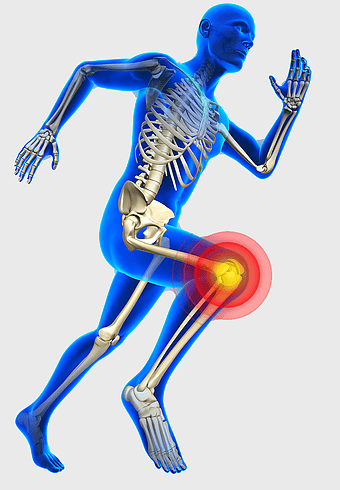

knee pain sports injury, physical therapy for athletes, human knee bones anatomy, joint focus in running, skeletal health in sports, musculoskeletal injury prevention, running biomechanics analysis -

blue man running anatomy, elastic therapeutic tape for pain, True Balance Chiropractic running therapy, human body joint pain, athletic injury recovery, skeletal health visual, mobility rehabilitation physics -